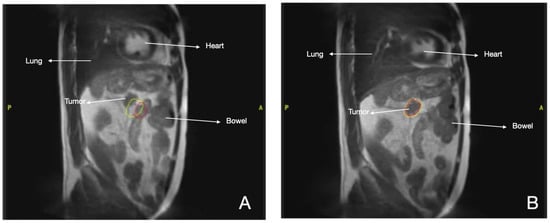

3.2. Lung Cancer

- Finazzi, T.; Palacios, M.A.; Haasbeek, C.J.; Admiraal, M.A.; Spoelstra, F.O.; Bruynzeel, A.M.; Slotman, B.J.; Lagerwaard, F.J.; Senan, S. Stereotactic MR-guided adaptive radiation therapy for peripheral lung tumors. Radiother. Oncol. 2020, 144, 46–52. [Google Scholar] [CrossRef]

- Koste, J.R.V.S.D.; Palacios, M.A.; Bruynzeel, A.M.; Slotman, B.J.; Senan, S.; Lagerwaard, F. MR-guided Gated Stereotactic Radiation Therapy Delivery for Lung, Adrenal, and Pancreatic Tumors: A Geometric Analysis. Int. J. Radiat. Oncol. Biol. Phys. 2018, 102, 858–866. [Google Scholar] [CrossRef]